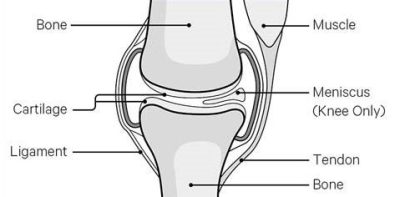

How does the knee work?

The knee is the largest joint in your body, found between your thigh and shin.

The knee joint is supported by strong ligaments, muscles and tendons which give stability, and menisci (cartilage) which act as shock absorbers all allowing the knee to move.